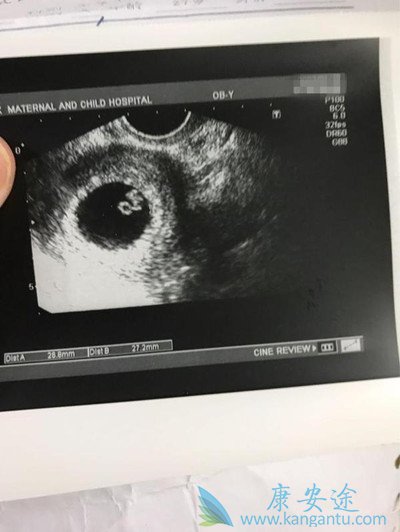

幸运是我

等到第10天又去医院检查,医生说宝宝暂时正常。等到第30天左右的时候,小腹有一点点胀痛,老公生怕出什么问题,紧张着又跑去医院,医生安慰我们说宝宝有胎心胎芽,一切都挺好的。我们这才放下心来,真是幸福到哭!